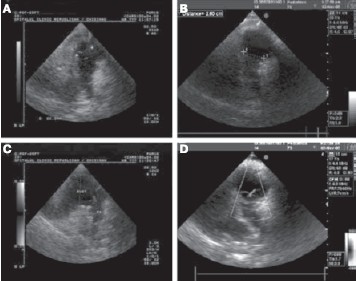

Хирургами нашей клиники (А. Haverich, А. Ciubotaru) в 2002 г. были проведены первые операции в детской клинике по имплантации тканево-инженерных клапанов, полученных на основе аутологичных клеток. Мононуклеарные клетки были изолированы из периферической крови детей и засеяны на децеллюляризированный аллогенный легочный клапан. После 21-го дня культивирования в биореакторе данные клапаны были имплантированы для реконструкции выводного тракта правого желудочка. Использование нами в целях тканевой инженерии аутологичных клеток не сопровождалось развитием иммунных реакций и признаков инфекции клапанов в послеоперационном периоде. Более того, наблюдение в динамике этих больных (более 7,5 лет) позволило констатировать не только нормальную функцию этих клапанов, но и признаки роста, подтвердив потенциал к ремоделированию и росту клапанов в зависимости от соматического развития ребенка [50] (рис. 5).

Рисунок 5. 2D-эхокардиограмма, выполненная через 3 мес (А) и 3,5 года (В) после имплантации легочного клапана. Регургитация клапана (допплеровский режим) через 3 мес (С) и 3,5 года (D) после операции (по [35]).

С 2005 г. нами выполняются операции с использованием децеллюляризированных кондуитов без аутологичных клеток. В настоящий момент проведены имплантации легочного кондуита более 40 пациентам. Возраст пациентов составлял от 2 мес до 21 года. Показаниями к операции являлись тетрада Фалло, стеноз легочного клапана, недостаточность легочного клапана, атрезия легочного клапана, транспозиция магистральных артерий с легочным стенозом, операция Росса. В настоящее время мы не имеем случаев повторных операций по поводу несостоятельности данных кондуитов. Данные эхокардиографии и магнитно-резонансной томографии сердца, выполняемых в динамике, показывают отсутствие дилатации или стеноза, кальцификации и дегенерации легочного клапана. Регургитация клапана соответствует степени 0—1 во всех случаях, трансвальвулярный градиент и конечный диастолический диаметр правого желудочка остаются стабильными.